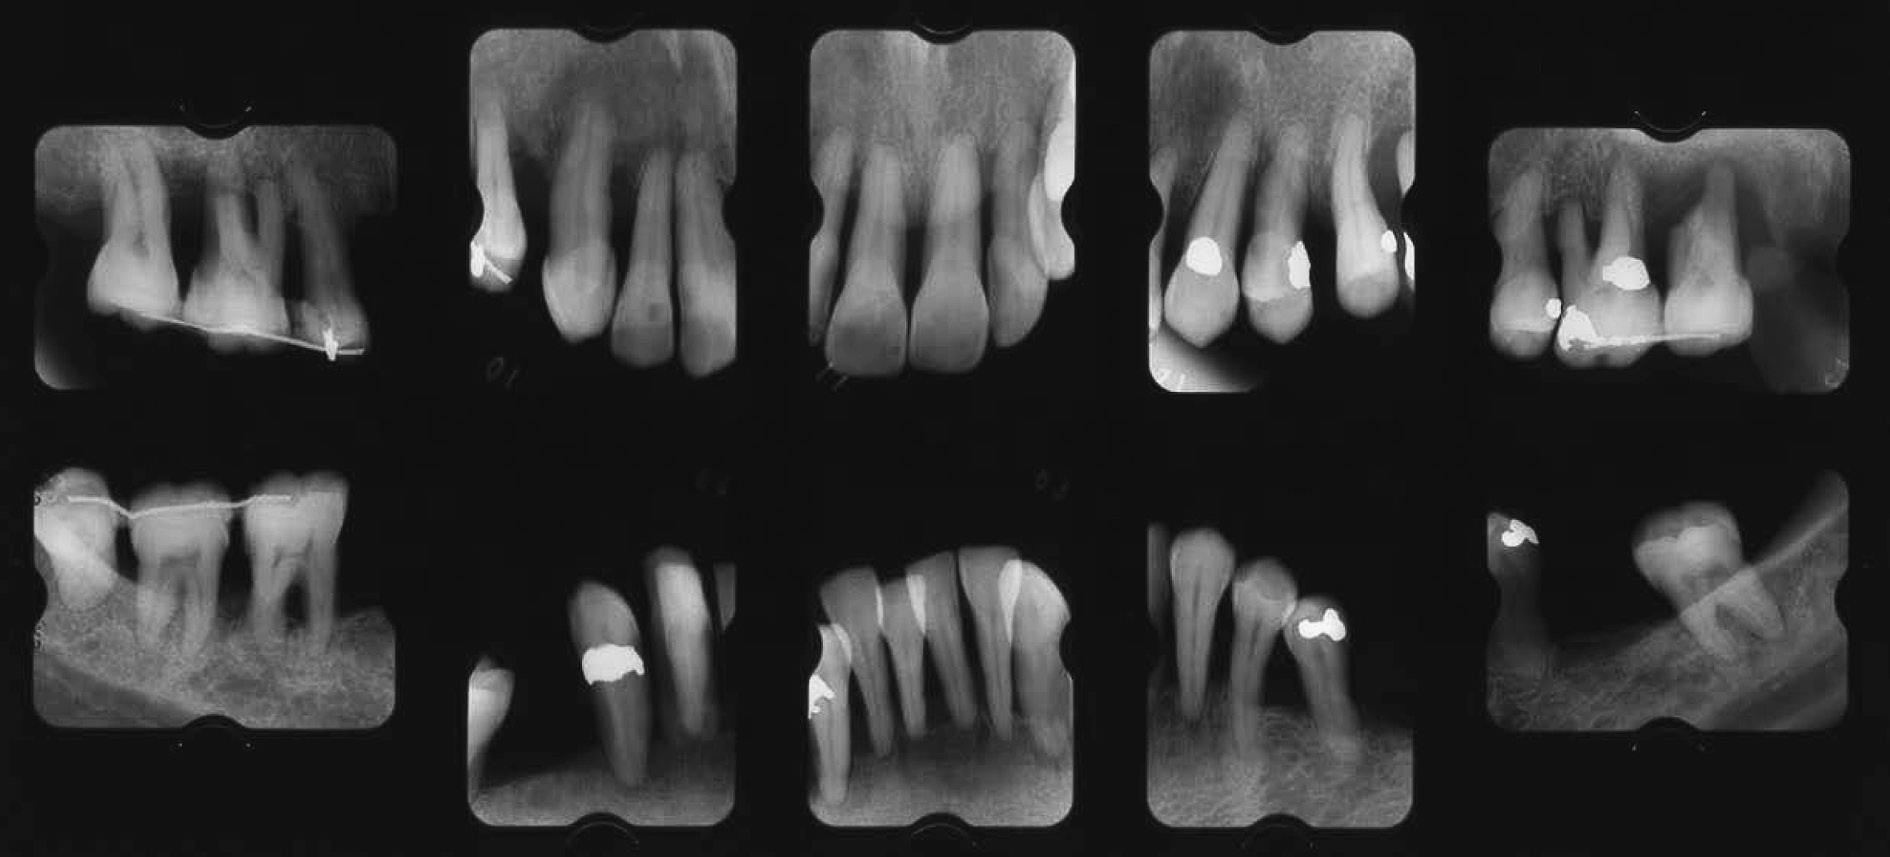

b) 治療方針と治療計画広汎型重度慢性歯周炎で喫煙関連性歯周炎でもある(図2,図3)。市場でご主人と天ぷらを揚げて販売している。仕事が多忙で,毎日疲労感が強く,睡眠も十分に取れない。重大な悩み事を持っている(内容不明)。細身体で,明らかにタバコ臭がある。歯周組織検査後,病状の説明を行い,治療計画を説明した。その際,希望があれば「禁煙指導」をする旨伝えたが,受諾はなかった。当時(平成6年)は現在ほど禁煙キャンペーンに熱心ではなかったことも災いしている。しかし,歯肉退縮,年齢42歳でかなりやせ型,タバコ臭と喫煙の悪影響がみられ,深いポケット残存部へのフラップ手術も計画しづらく,また再発の危険性も高いため,プラークコントロールレベルの改善に加えて禁煙達成を歯周外科手術実施の条件として計画を立てた。患者から得られた情報は歯周組織所見(図2)として歯根露出(歯肉退縮),歯の挺出,歯の着色,歯石沈着等であった。歯肉に発赤・腫脹の炎症所見が認められる。同様に,エックス線写真(図3)より,全顎的に高度な歯槽骨吸収がみられ,37および47は既に欠損し,17,16,12,11,22,24,25,26,27,31,41,42はほぼ根尖に至る骨吸収像,上下大臼歯はすべて根分岐部病変に罹患していることが分かった。

初診時(42歳,女性)のエックス線写真。